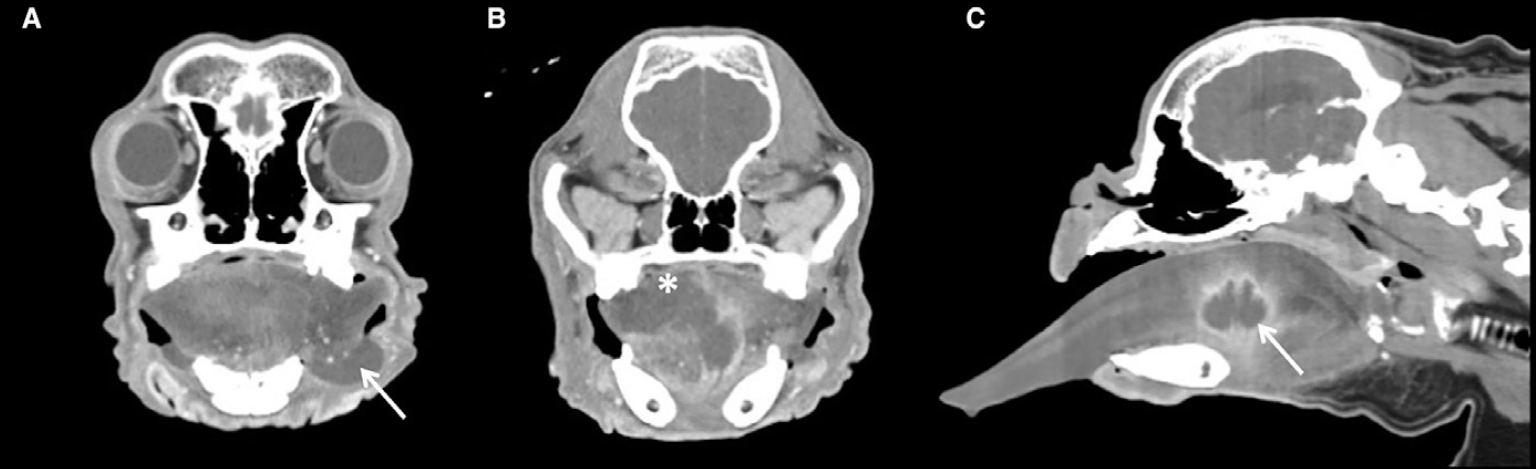

첫째, CT 검사를 통해 병변의 형태와 범위를 확인했습니다.

급성으로 발생한 혀 부종과 종괴 소견을 바탕으로 알레르기 반응, 외상, 이물, 종양성 변화 등이 감별진단으로 고려되었고 이에 따라 CT 검사가 진행되었습니다.CT 결과 혀는 현저히 커져 있었으며 혀의 뿌리에서 몸통까지 이어지는 공동성 병변이 확인되었습니다.

또한 조영 후 영상에서는 rim enhancement가 관찰되어 설농양을 시사하는 소견으로 판단되었습니다.